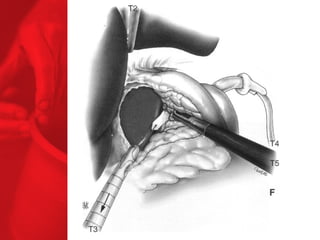

GASTRIC BYPASS Lesprocédures de malabsorption et restrictives > 56% de perte de poids excédentaire après quatre ans* > diminue le diabète de type 2 chez plus de 83 % des patients* *Christou NV, Sampalis JS, Liberman M, et al. Surgery Decreases Long-Term Mortality, Morbidity, and Health Care Use in Morbidly Obese Patients. Annals of Surgery 2004;240(3):416-424. ** Buchwald H, Avidor Y, Braunwald E, et al. Bariatric Surgery—A Systematic Review of the Literature and Meta-analysis. Journal of the American Medical Association 2004 Oct 13;292(14).

Echecs Malgré unebonne technique du CCGL, des échecs surviennent chez 15 à 20 % des patients. Les causes de reprise pondérale sont la dilatation de la poche gastrique, la dilatation de l'anastomose gastrojéjunale, l'hypertrophie des villosités du jéjunum proximal et la prise d'une alimentation avec des liquides à haute teneur en calories. Ainsi, pour les « superobèses » pathologiques (IMC > 50 kg/m2), l'intervention de référence pourrait devenir la diversion biliopancréatique.

COMMENT FONCTIONNE LECOURT-CIRCUIT GASTRIQUE ? Facteurs chirurgicaux Restriction du volume des repas Certaine malabsorption Syndrome de chasse Réduction de l'appétit Facteurs pour les patients Apport en calories Dépense en calories BILAN ENERGETIQUE = apport alimentaire dépense en énergie

Points importants •  La GVC est plutôt indiquée pour l'adulte hyperphage, sans trouble majeur du comportement alimentaire, même s'il existe une hernie hiatale avec un RGO non sévère, II peut être fait un geste antireflux. Ce geste est proposé aussi aux patients refusant un anneau modulable implantable (et boîtier d'ajustage). •  Le CCG ou bypass gastrique (court-circuit gastrojéjunal) est proposé à l'adulte « superobèse » (IMC > 50 kg/m2), ayant des troubles du comportement alimentaire (compulsif), une hernie hiatale avec un RGO, associée à une œsophagite très sévère. II est proposé en seconde intention en cas d'échec des interventions de restriction gastrique.  •  La technique de gastrectomie pariétale en gouttière avec diversion biliopancréatique est à réserver aux « superobèses » (IMC > 60 kg/m2) et au syndrome de Prader-Willi. •  La gastrectomie longitudinale en manchette, le cerclage gastrique modulable au la gastroplastie verticale bandée peuvent faire maigrir les « superobèses » avant de leur proposer une chirurgie de malabsorption en seconde intention et avec un moindre risque chirurgical sous laparoscopie.